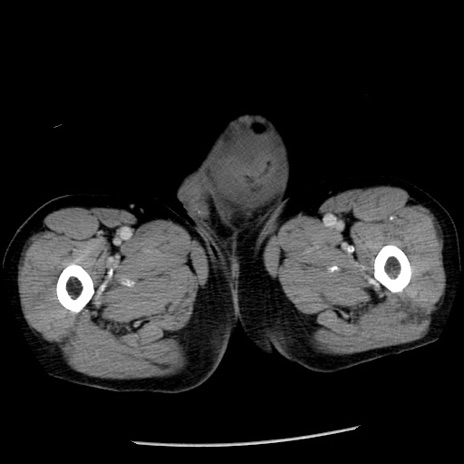

症例26(横断像)

【症例】80歳代男性

【主訴】嘔吐

【現病歴】昨晩2回嘔吐あり、今朝になっても嘔吐あり。来院。

【既往歴】胃潰瘍

【身体所見】意識清明、BT 37.6℃、BP 166/95mmHg、HR 100bpm、SpO2 97%、腹部:平坦・軟、腸蠕動音聴取良好、圧痛なし。

【データ】WBC 21900、CRP 1.46